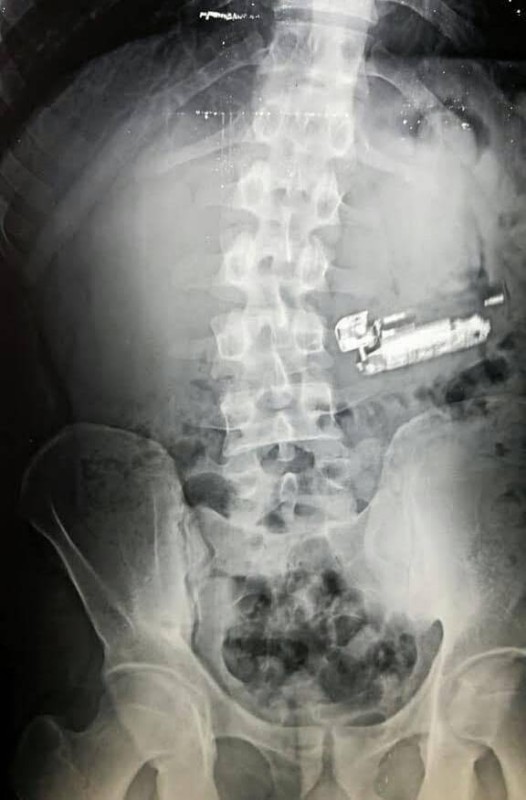

في واقعة غريبة، تمكن فريق طبي بمستشفى المنصورة الدولي العام الجديد شمال مصر، من استخراج جوال وولاعة وعملات معدنية من بطن مريض كان يعاني من آلام شديدة بالبطن والمعدة.

واستقبل المستشفى مريضاً يعاني من آلام شديدة في البطن وبعد إجراء الفحوصات تبين وجود أجسام غريبة في معدته، وعلى الفور قرر الأطباء إجراء جراحة عاجلة.

وفوجئ الفريق الطبي خلال الجراحة بوجود جوال وولاعة سجائر وبعض العملات المعدنية داخل معدته، وتم استخراجها مع وضع المريض تحت الملاحظة الطبية.

وقال مدير المستشفى الدكتور أحمد حشيش، إن المريض شاب يبلغ من العمر 30 عاما، وإن الأشياء الغريبة التي استخرجت من معدته كانت كفيلة بإحداث تسمم له ومن ثم وفاته، مشيراً إلى وجود جسم غريبة آخر تم استخراجه، ولكن ظل مجهولاً لتغير معالمه في بطن المريض.